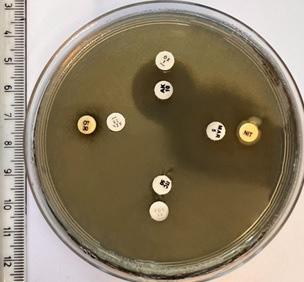

Figura 2 (a, b). S. maltophilia pe mediul Mueller-Hinton și detaliu (foto original)

1.3 STENOTROPOHOMONAS MALTOPHILIA

S. maltophilia (Fig. 2 a, b), o specie relativ nouă, care este parte constituentă a familiei Xanthomonadaceae , familie care grupează peste 25 de genuri. Denumirea genului provine din cuvinte grecești ( stenos = îngust; trophe = hrană și monas = o unitate). Ulterior, au fost identificate și alte specii: S. acidaminiphila, S. nitrireducens, S. africana, S. rhizophila etc. (5)

1.3.3. Morfologie, caractere culturale și proprietăți biochimice

S. maltophilia este o bacterie Gram negativă, uniformă morfologic, care apare sub forma unui bacil scurt, subțire, drept sau curbat, cu dispunere izolată sau în perechi, non-fermentativ. Prezintă mobilitate datorită a doi sau mai mulți flageli polari. Cultivarea se face în condiții aerobe. Temperatura optimă de creștere este de 35°C. Coloniile sunt netede, cu contur regulat și de culoare albă-cenușie sau galben pal. Culoarea se poate intensifica la o temperatură mai ridicată de 42°C. Are o capacitate nutrițională restrânsă (5)

Tulpina S. maltophilia a fost izolată din apă florală utilizată în industria cosmetică, iar tulpina de P. aeruginosa din cavitatea bucală a unui șarpe (cobra imperială) cu bronșită recurentă.

Plăcile din toate seriile au fost incubate timp de 24 de ore, la 37 °C, după care s-a efectuat citirea (măsurarea) și interpretarea rezultatelor.

2.3.1. SERIA 1

Pentru placa 1 cu S. maltophilia (Fig. 3), din cadrul primei serii, s-au dovedit active următoarele antibiotice, în ordinea descrescătoare a eficacității: Marbofloxacina, Kanamicina, Ofloxacina, Lincocin forte, Rifampicina și Neomicina. Pentru Spiramicină și Penicilină s-a constatat fenomenul de antibiorezistență.

Pentru placa 1 cu P. aeruginosa (Fig. 4), din cadrul primei serii, s-au dovedit active următoarele antibiotice, în ordinea descrescătoare a eficacității: Kanamicină, Lincocin forte, Marbofloxacină și Neomicină. Pentru Spiramicină, Rifampicină, Ofloxacină și Penicilină s-a constatat fenomenul de antibiorezistență.

2.3.2. SERIA 2

În cadrul celei de a doua serii de plăci, au fost folosite combinații a câte două antibiotice. Acestea au fost alese atât raportat la rezultatele obținute în prima serie, cât și în funcție de diferite studii de specialitate și recomandări clinice.

La nivelul plăcii 1, cu S. maltophilia (Fig. 13), din cadrul celei de a doua serii, s-au dovedit active următoarele combinații de antibiotice, în ordinea descrescătoare a eficacității: Tobramicină + Lincocin, Florfenicol + Neomicină, Kanamicină + Lincocin forte și Florfenicol + Piperacilină. Nu s-au constatat fenomene de antibiorezistență.

La nivelul plăcii 1, cu P. aeruginosa (Fig. 14), din cadrul celei de a doua serii, s-au dovedit active următoarele combinații de antibiotice, în ordinea descrescătoare a eficacității: Tobramicină + Lincocin, Florfenicol + Neomicină, Kanamicină +Lincocin forte, Piperacilină + Florfenicol. Nu s-au constatat fenomene de antibiorezistență.